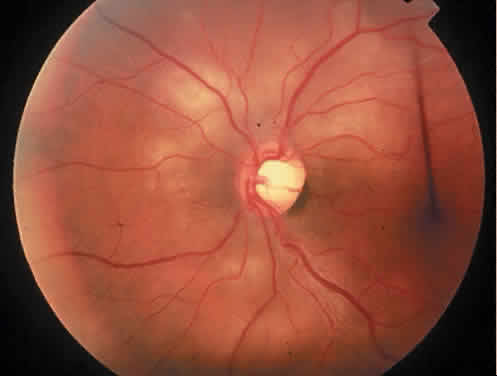

The most common ocular manifestations of TTP include papilledema, extraocular muscle palsies, and visual field defects, which usually are secondary to concomitant CNS involvement.75 Retinal findings consist of hemorrhages, retinal vascular occlusions, and serous detachments76,77 (Figs. 8 to 10). The cause of the serous detachments appears to be focal occlusion of the choriocapillaris resulting in retinal pigment epithelial damage and blood-retinal barrier disruption.76,77 Findings on fluorescein angiography are characterized by focal areas of nonperfusion of the choriocapillaris associated with late leakage into the subretinal space76 (Fig. 11). This is consistent with histopathologic studies that show occlusion of the choriocapillaris and large choroidal vessels, presumably by fibrin, with overlying necrosis of thepigment epithelium.75,76 TTP also has been linked in one case report with Purtscher retinopathy.78

Fig. 8. Patient with thrombotic thrombocytopenic purpura and extensive retinal vascular-occlusive disease. (Courtesy of William Mieler, MD.)

Fig. 9. Fluorescein angiogram of patient with thrombotic thrombocytopenic purpura and vascular-occlusive disease. (Courtesy of William Mieler, MD.)

Fig. 10. A 42-year-old woman with thrombotic thrombocytopenic purpura and neurosensory retinal detachments. (Courtesy of Jerry Neuwirth, MD.)

Fig. 11. Fluorescein angiogram of patient with thrombotic thrombocyto-penic purpura showing late choroidalhyperfluorescence caused by focal areas of choriocapillaris nonperfusion. (Courtesy of Jerry Neuwirth, MD.)